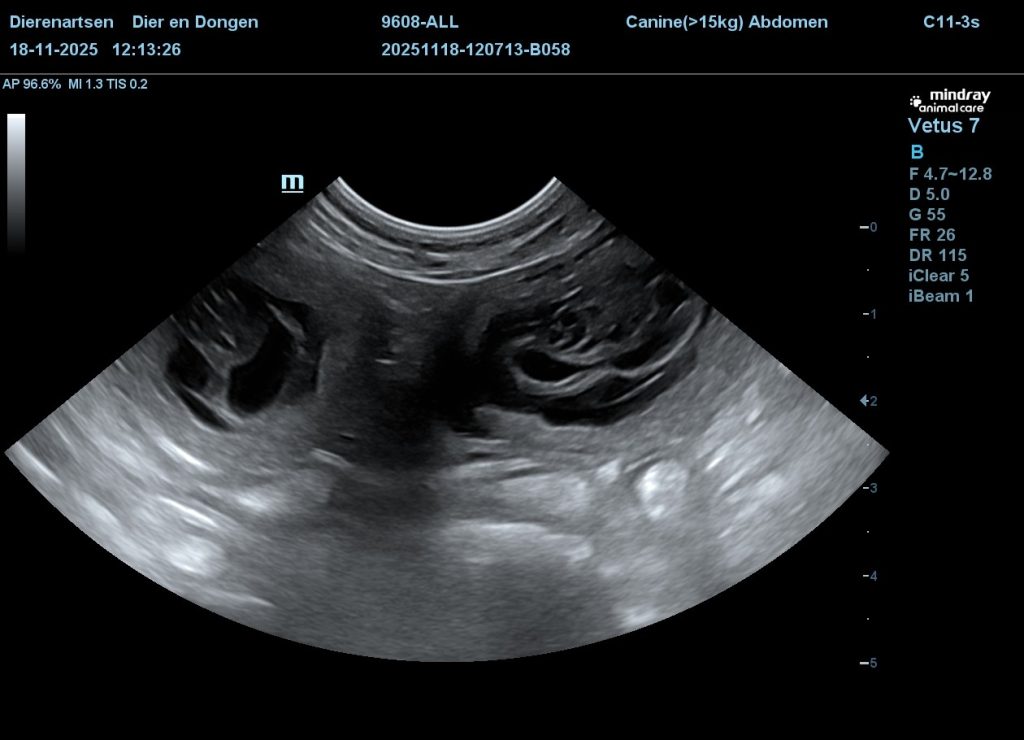

Met 4 weken hebben we een echo laten maken en Allie blijkt dragend te zijn.

We kunnen rond kerst dus een aantal pups verwachten.

Nu verwachten we geen groot nest want Allie heeft nooit echt grote nesten. Maar dat er een paar pupjes in aanmaak zijn is duidelijk!